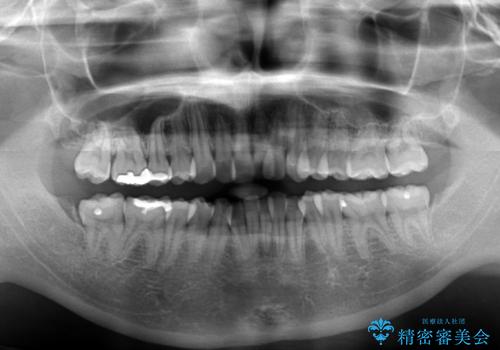

- 上下の出っ歯を気にして来院された患者様です。

口元を積極的に引っ込めるために、上下左右の第一小臼歯を4本抜歯することとしました。

下顎の正中を上顎に合わせる処置が難航し、期間が長引きました。

最終的には上下の正中も合い、横顔の印象が変わるほどスッキリとした口元となりました。